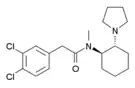

| Opioid peptides | Skeletal molecular images |

| Adrenorphin |  |